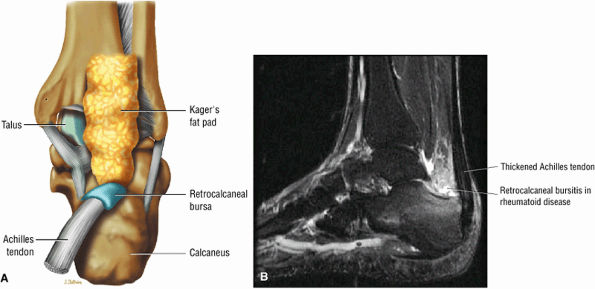

-

Achilles tendinitis is subdivided into non-insertional tendinosis and insertional tendinitis.

The Achilles tendon has no synovial sheath but is associated with a paratenon or connective tissue envelope.

MR identifies nodular or convex tendon thickening and intratendinous mucoid degeneration.

Haglund's deformity represents insertional tendinitis with a posterosuperior calcaneal bony prominence and retrocalcaneal tendo Achilles bursitis.

In tendinosis or tendinopathy, there is intrinsic or intrasubstance degeneration of the Achilles tendon.

Tendinitis represents the clinical symptoms that develop in association with the degenerative process of tendinosis.

In paratendinitis (also known as peritendinitis, since it refers to the peritendinous tissues), there is generalized inflammation of the tissues surrounding the Achilles tendon (pre-Achilles fat).32

In paratendinitis (peritendinitis) (Fig. 5.106) with tendinosis, there is inflammation of the surrounding tissues with associated tendon degeneration.

The paratenon (also referred to as the peritenon) represents the connective tissue envelope surrounding the Achilles tendon.

Paratenonitis is an inflammation of the Achilles tendon connective tissue envelope (usually limited to the posterior paratenon on MR images).

An irregular pre-Achilles fat pad may be seen with paratendinitis (peritendinitis) with or without abnormal Achilles tendon morphology.